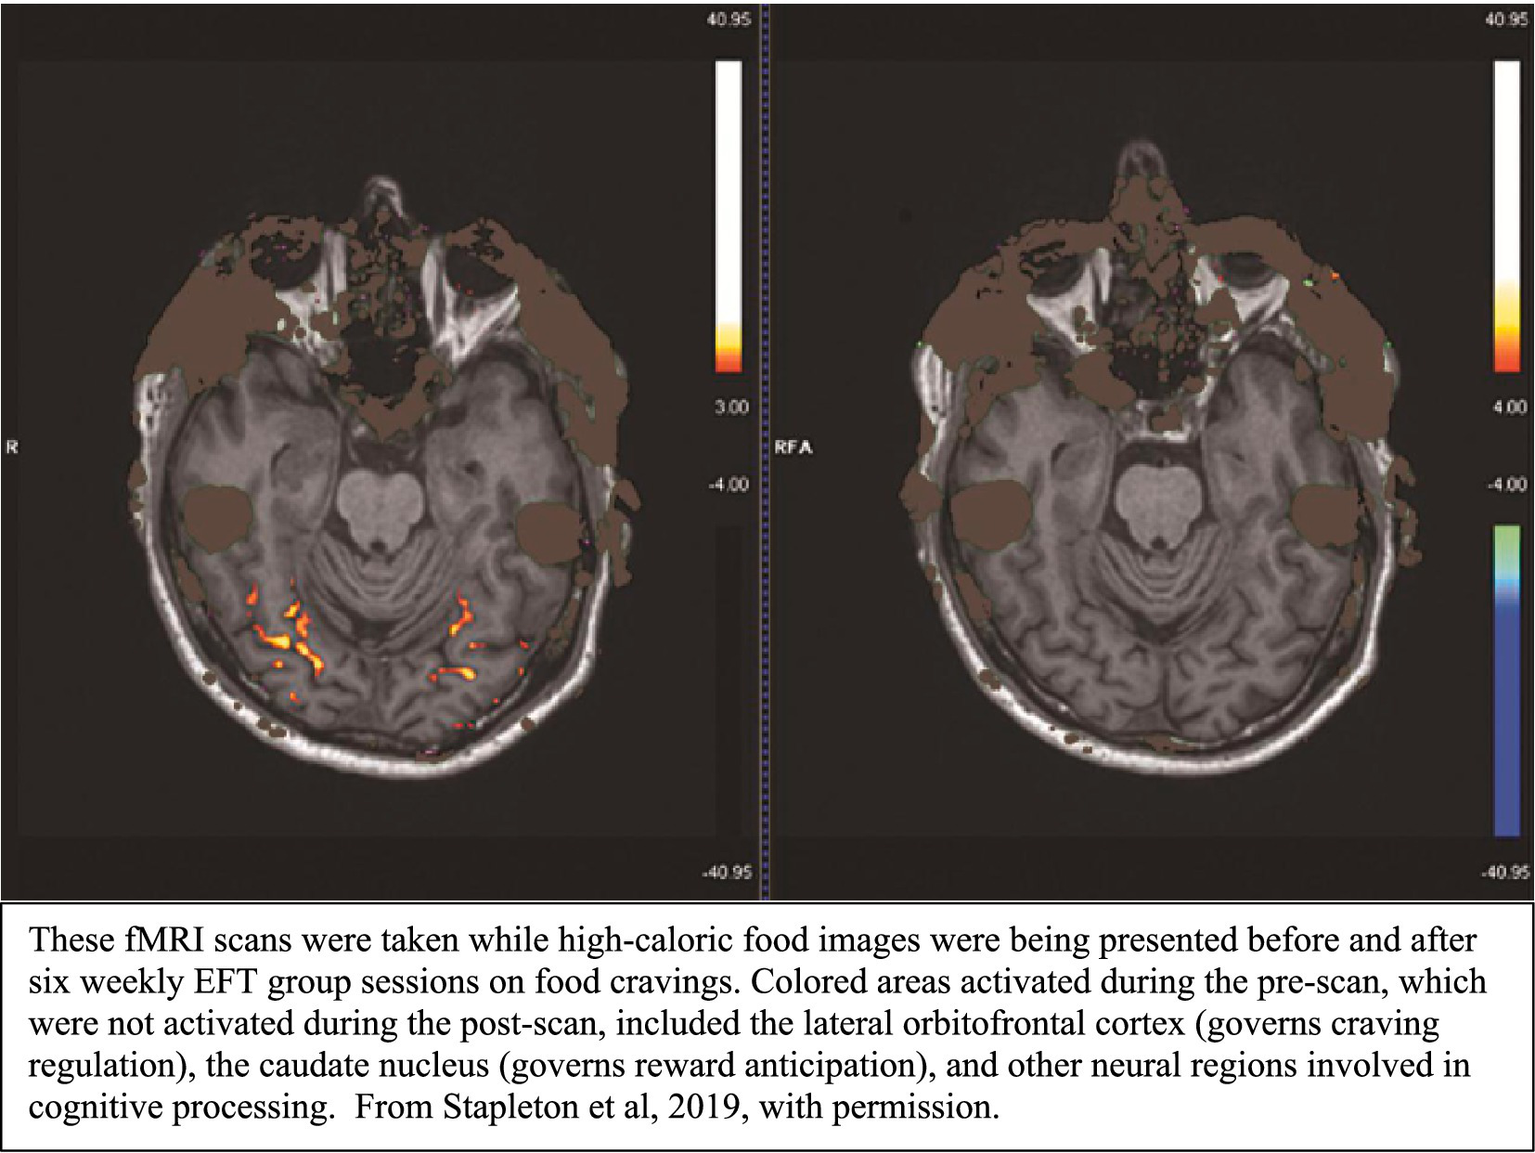

Once the signals generated by tapping reach the brain regions activated by the client’s recalled memory, problem, or goal, they initiate immediate neural modulation within those circuits. The imaging studies of acupoint tapping indicate that tapping can both downregulate areas linked to emotional distress and upregulate regions associated with cognitive control and adaptive behavior. For example, separate studies showed how EFT altered neural activity in individuals with food cravings (Stapleton et al., 2019) and chronic pain (Stapleton et al., 2022). Both studies reported that downregulation of these regions was associated with and appeared to lead to symptom improvement in participants (see Figure 1).

Figure 1

Pre- and post-treatment fMRI scans.